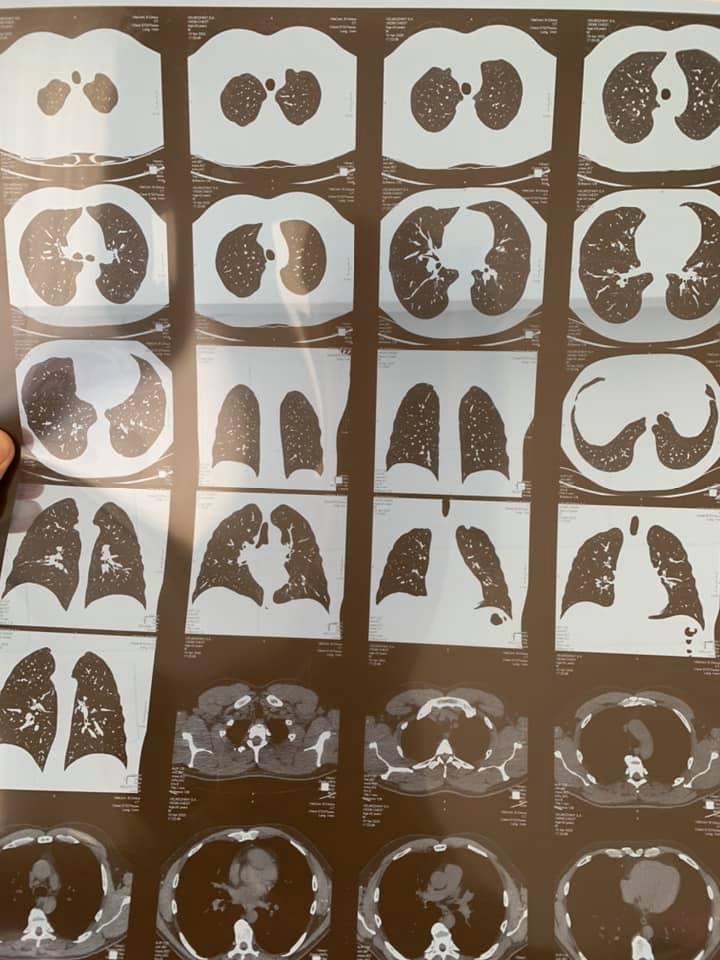

"К сожалению, мои друзья, это случилось. Прошел компьютерную томографию легких. Результат - двухсторонняя пневмония... Нет слов, я подавлен…" – говорится в сообщении.

Также Вельможный опубликовал снимки, сделанные в ходе визита в больницу.